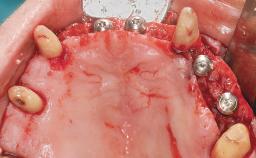

Conventional Loading of Eight Implants in the Maxilla and Final Restoration with a Full-Arch Gold-Ceramic FDP

A 35-year-old Caucasian female presenting with advanced periodontal disease involving both the maxillary and the mandibular dentition was referred for evaluation. The patient, a non-smoker in good general health, requested treatment for recurrent periodontal abscesses, tooth mobility, and discomfort during chewing, as well as restoration of her missing teeth with a fixed prosthesis to improve mastication and esthetics. All residual maxillary teeth exhibited plaque deposits, deep pockets, bleeding on probing, and class III mobility and were evaluated as hopeless. All residual mandibular teeth except tooth 37 could be maintained after periodontal therapy.